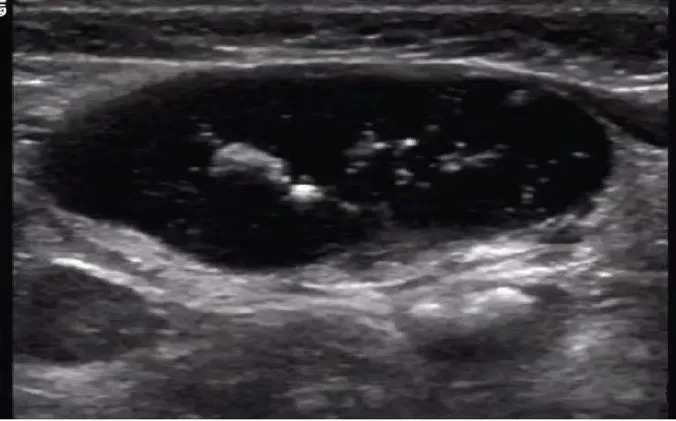

左腋下淋巴结结核样肉芽肿性炎并坏死及钙化。

病例:1岁男孩,发现腋窝包块2个月,质地较硬,患儿无明显发热。

超声描述:左侧腋窝可见两个混合回声团,边界清楚,内部回声不均匀,可见多个强回声点,未见明显淋巴结结构。内部见杂乱血流信号。